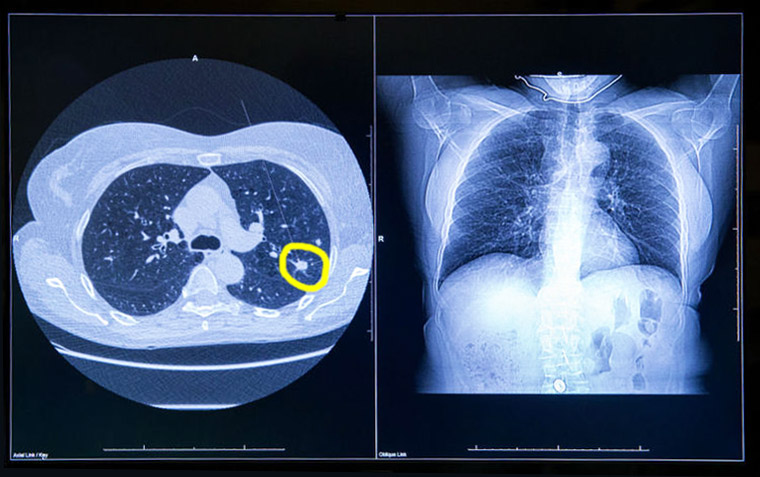

Tamizaje para cáncer de pulmón: riesgos de la radiación acumulada

La exposición a múltiples tomografías computadas de baja dosis y a tomografías por emisión de positrones resulta en un riesgo identificable de inducción de cáncer de pulmón y de otros tumores, pero que resulta muy inferior a la reducción esperada de mortalidad por el rastreo. BMJ, 8 de febrero de 2017